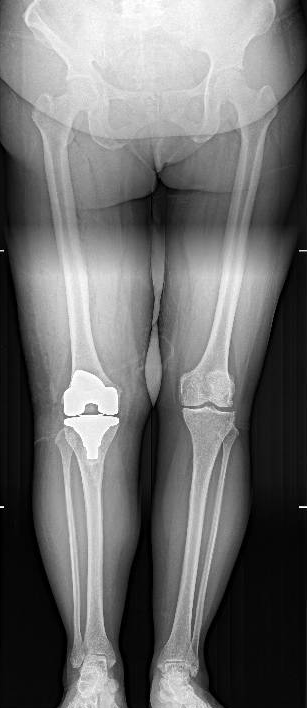

D打印个性化手术导板成功助力复杂人工膝关节置换手术,化繁为简!

全膝关节表面置换术(totalkneearthroplasty,TKA)是治疗严重膝关节疼痛及畸…